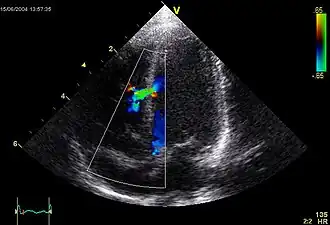

Image en échocardiographie doppler couleur : le flux vert témoigne d'un passage de sang entre le ventricule gauche et le ventricule droit à travers le septum

En pratique, l'échocardiographie doppler, examen non douloureux et non irradiant suffit pour poser un diagnostic précis de la malformation et sauf exception pour apprécier son retentissement et sa gravité. L'image ci-contre nous montre une turbulence sanguine (en vert) traversant la paroi inter ventriculaire (ligne verticale en gris), et allant d'un ventricule à l'autre (cavités ventriculaires en noir). Le doppler permet de quantifier le shunt (calcul du rapport du débit systémique sur débit pulmonaire). Cet examen permet également de détecter des anomalies cardiaques associées, d'évaluer le retentissement sur le ventricule droit et d'estimer les pressions des cavités cardiaques droites.